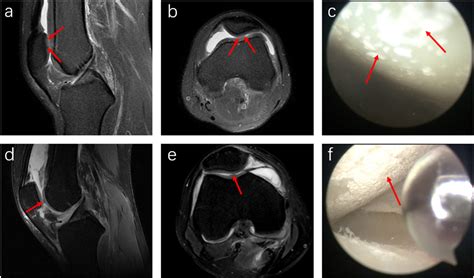

⚠️ Note: If you suspect you have gout in knee, do not attempt to self-diagnose. Only a healthcare professional can confirm the diagnosis, often by drawing fluid from the joint to test for uric acid crystals.